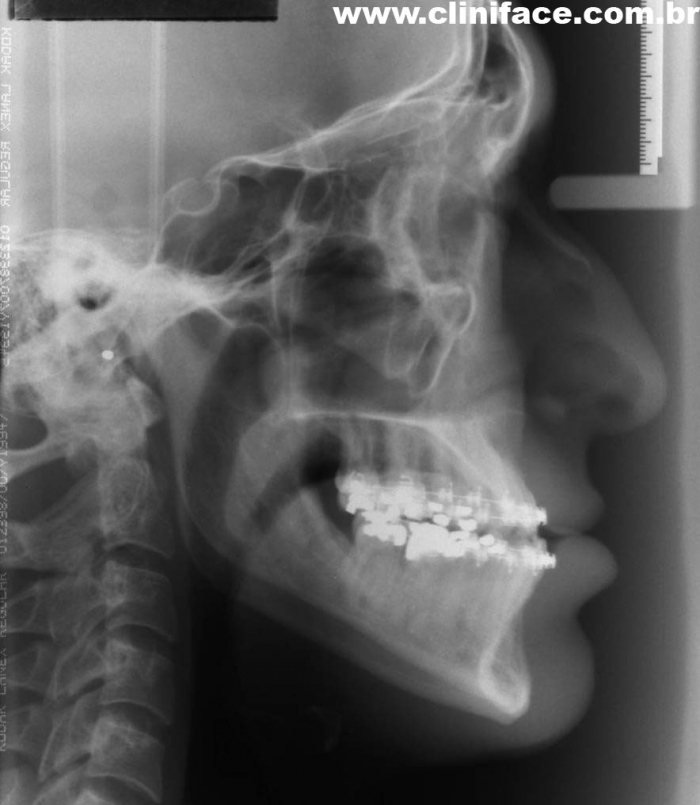

Telerradiografia inicial